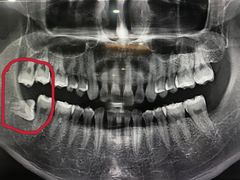

• 众鑫医疗小白牙口腔(土桥店)

• -众鑫医疗小白牙口腔(土桥店)

赴 | 20-09-06